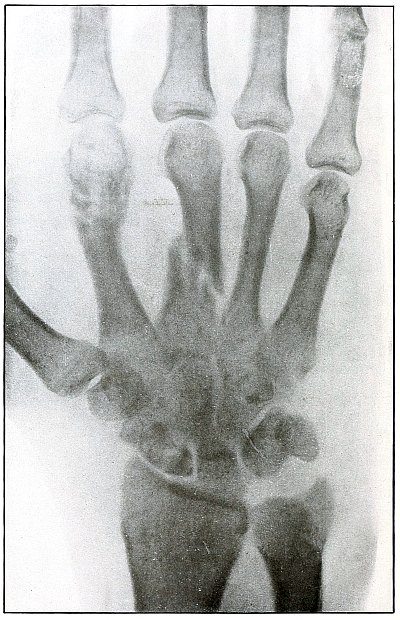

[Pg 98]

Plate 44.

[Pg 99]

Rifle—Plate 44.

UPPER EXTREMITY.

Gunshot Fracture of the Third Phalanx.

The course of the bullet was anteroposterior through the base of the

proximal phalanx of the middle finger, with a velocity of long range.

It practically punctured the bones and split off a few fragments

without displacement.

The wound of entrance would be much the same as the wound of exit,

with the latter, but a little larger.

Treatment is conservative.